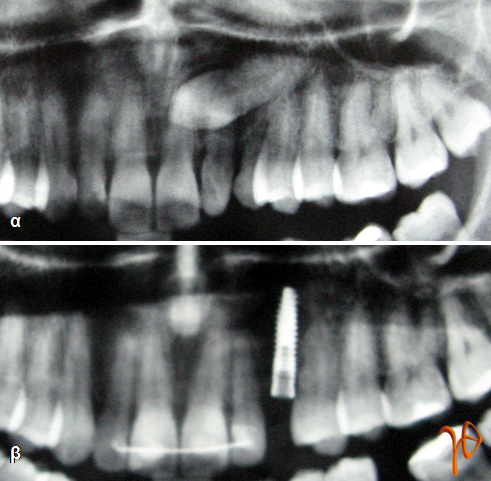

Νεαρή γυναίκα μετά από ορθοδοντική θεραπεία προσήλθε για την αφαίρεση του εγκλείστου άνω αριστερού κυνόδοντα. Στην πανοραμική ακτινογραφία ο έγκλειστος κυνόδοντας σχημάτιζε γωνία 70 μοιρών με τη μέση γραμμή και η κορυφή του έφτανε έως εγγύς της ρίζας του κεντρικού τομέα, μέχρι την ρινική άκανθα, χωρίς όμως να διασχίζει την μέση γραμμή(Εικόνα 1α).

Εικόνα 1. Πανοραμική ακτινογραφία. 1α: Ο έγκλειστος κυνόδοντας, 1β: Το οδοντικό εμφύτευμα.

Η χειρουργική προσπέλαση έγινε υπερώια, όπου και ο έγκλειστος εντοπίστηκε να βρίσκεται σε στενή σχέση με τις ρίζες του κεντρικού και πλαγίου τομέα, αλλά και του πρώτου προγομφίου. Μαζί με τον έγκλειστο αφαιρέθηκε και ο νεογιλός κυνόδοντας που κλινικά εμφάνιζε έντονη ευσειστότητα. Μετά από δυόμισυ μήνες τοποθετήθηκε οδοντικό εμφύτευμα (ΧΙVE 3,4/15) (Εικόνα 1β) και μετά από άλλους δύο μήνες τοποθετήθηκε η τελική προσθετική εργασία(Εικόνα 2α-δ).